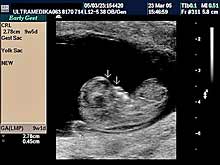

A) I trimestar do 14

nedelje gestacije

(3 meseca + 2 nedelje)

Indikacije za ultrazvučni pregled:

- Izostanak menstruacije, procena vitalnosti rane trudnoće,

procena materične i/ili postojanje vanmaterične trudnoće.

(Od 4-7 nedelje gestacije, ili prva 2 meseca od prvog dana zadnje

menstruacije).